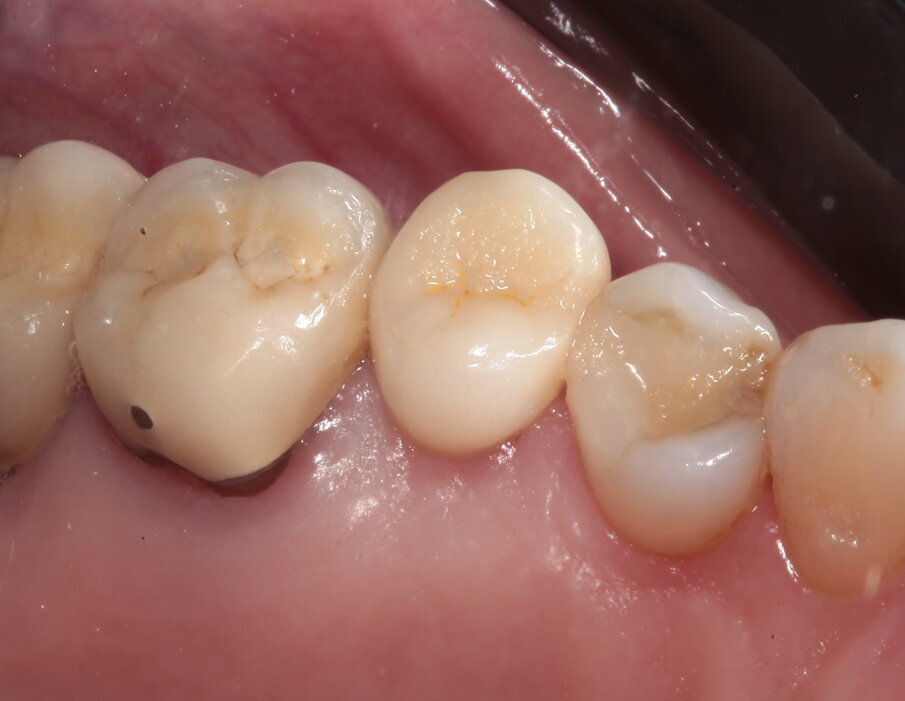

La paziente si presenta in visita lamentando mobilità e l’insorgenza di un dolore alla masticazione a carico dell’elemento 25. Clinicamente l’elemento presenta una corona in ceramica integrale realizzata anni prima (non ricorda quanti) presso altra sede, mobilità di II grado e sondaggio di 9 mm sul versante palatale.

Si presenta inoltre dolente alla percussione. Si riscontra anche l’assenza di risposta al test di vitalità dell’elemento 24, sul quale la paziente riferisce sia stata effettuata una medicazione endodontica da un collega come tentativo di risolvere la sintomatologia dolorosa a carico dell’elemento 25 (Figg. 1-3).